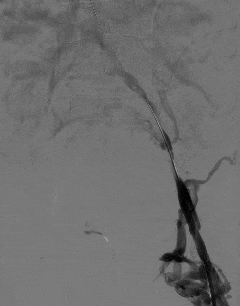

团队随即采用球囊扩张导管逐级对闭塞血管进行精准扩张,逐步恢复血管管腔通畅性。

术后即时评估显示,左下肢髂静脉恢复部分血流,肢体回流障碍得到有效改善。

李叔叔术后即刻反馈,左下肢憋胀感明显减轻,肢体比术前轻松了许多。